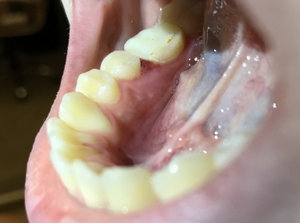

Доброго времени суток. Скажите пожалуйста: если болели зубы при накусывании в течение 2-х дней, болели не сильно, а потом прошли, то что это может быть? Спасибо.

Добрый день. В этом случае возможно на верхушках имеется воспаление. И оно, как правило, проявляется при снижении иммунитета. Я вам рекомендую обратится на очный прием к стоматологу-терапевту для составления плана лечения оперяясь на рентген снимки и на состояние зубов в полости рта. Запишитесь к нам на прием и мы обязательно вам поможем.